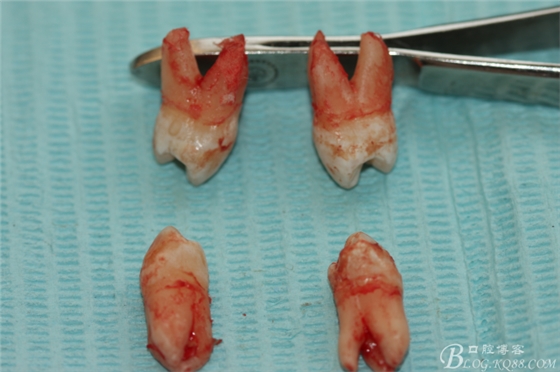

患者:江某某、男、14歲。因正畸治療需要拔除上下頜四顆第一前磨牙。按醫(yī)囑,局麻下拔除四顆第一前磨牙。牙齒拔除后發(fā)現(xiàn)四顆牙齒均為三個(gè)根,頰側(cè)兩根,腭側(cè)一個(gè)根。上頜第一前磨牙偶見(jiàn)三根。下頜第一前磨牙左右兩側(cè)均為三根,實(shí)屬罕見(jiàn)。發(fā)圖片,與同仁共勉。

7.四顆離體上下頜第一前磨牙牙根形態(tài)